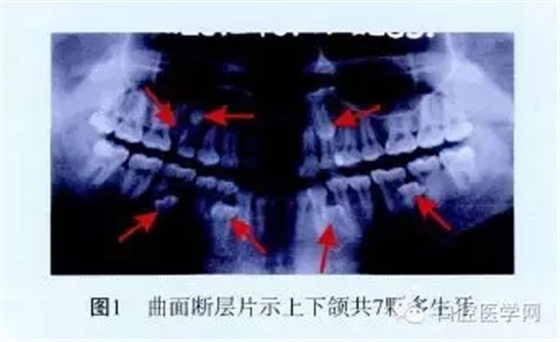

曲面斷層片顯示:15與16之間有2顆多生牙;23根尖1顆多生牙,牙冠與根尖重疊;43與44、33與34兩根尖1/3處各有1顆多生牙;36根尖可見(jiàn)1顆水平向多生牙,牙冠朝向37根近中,根尖與36根尖重疊;46根分叉下方有1顆多生牙;上下頜共有7顆多生牙(圖1)。